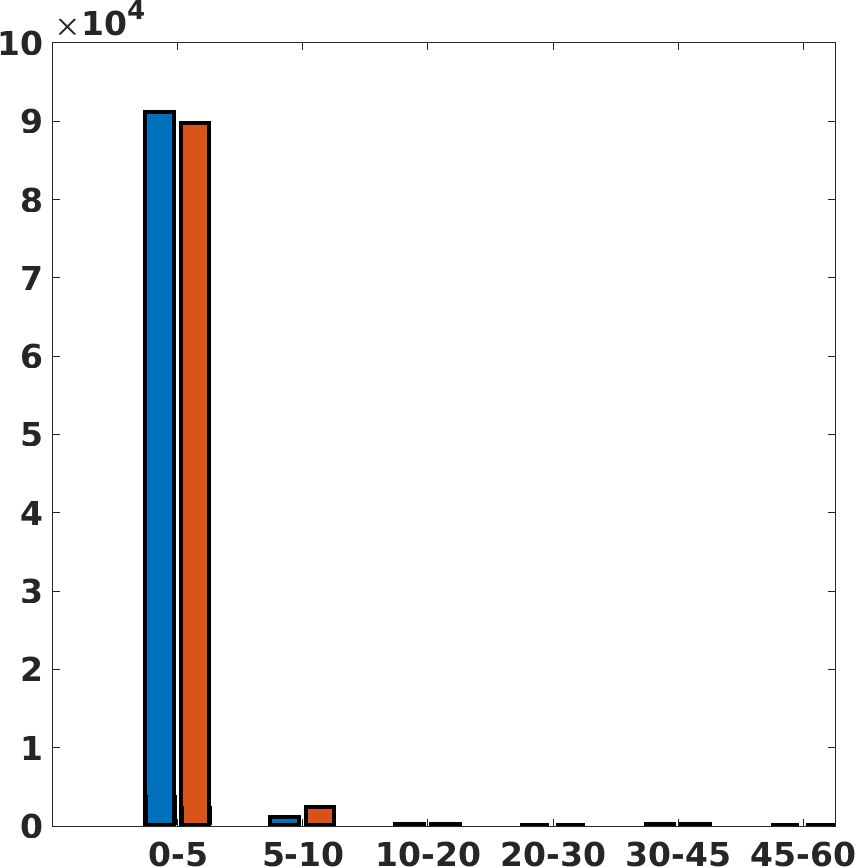

Fig. 7(a-b-c, right) shows the histogram of the absolute value of the error with respect to the target image, of the prediction and Cubic convolution results, respectively. The histograms show the number of pixels where the prediction error is lower than 5 (i.e., the first bin of the histogram), which means very similar to the target when visually analysing the images. From the Cubic convolution to the predicted images, this value increases of on obstetric 4X raw images, on cardiac 4X raw images, and on abdominal 4X raw images.

Fig. 17 (left) shows the box plot of the quantitative metrics, comparing the target images with the prediction and the Cubic convolution, respectively. The PSNR metric is computed on a data set of 200 images, belonging to the same district, and with the same up-sampling factor. Analysing the obstetric anatomical district and concerning the corresponding raw images (Fig. 7 (a, left)), the denoising allows the network to significantly improve the results of the up-sampling and the prediction. In particular, comparing the target images with the predicted images, the median PSNR value of obstetric 2X denoised images is 51.8, compared to the median PSNR value of obstetric 2X raw images which is 36.9.

Fig. 17 (right) shows the histogram of the absolute value of the error with respect to the target, of the prediction and Cubic convolution respectively. This result shows that our framework increase of and (2X and 4X, respectively) the number of pixels where the prediction error is lower than 5, which is very similar to the target when visually analysing the images, and improved with respect to the learning framework applied to raw images. According to Fig. 18, our method improves the accuracy of Cubic convolution. For example, the SSIM increases of on cardiac 2X and the MAE increases of on abdominal 4X.